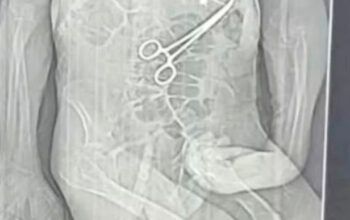

Além desse medicamento, o técnico de enfermagem apontado como principal suspeito usou uma seringa para fazer dez aplicações de desinfetante em uma das vítimas, uma mulher de 75 anos.

O principal suspeito é Marcos Vinícius Silva Barbosa de Araújo, de 24 anos. Também foram presas as técnicas de enfermagem Marcela Camilly Alves da Silva e Amanda Rodrigues de Sousa,...